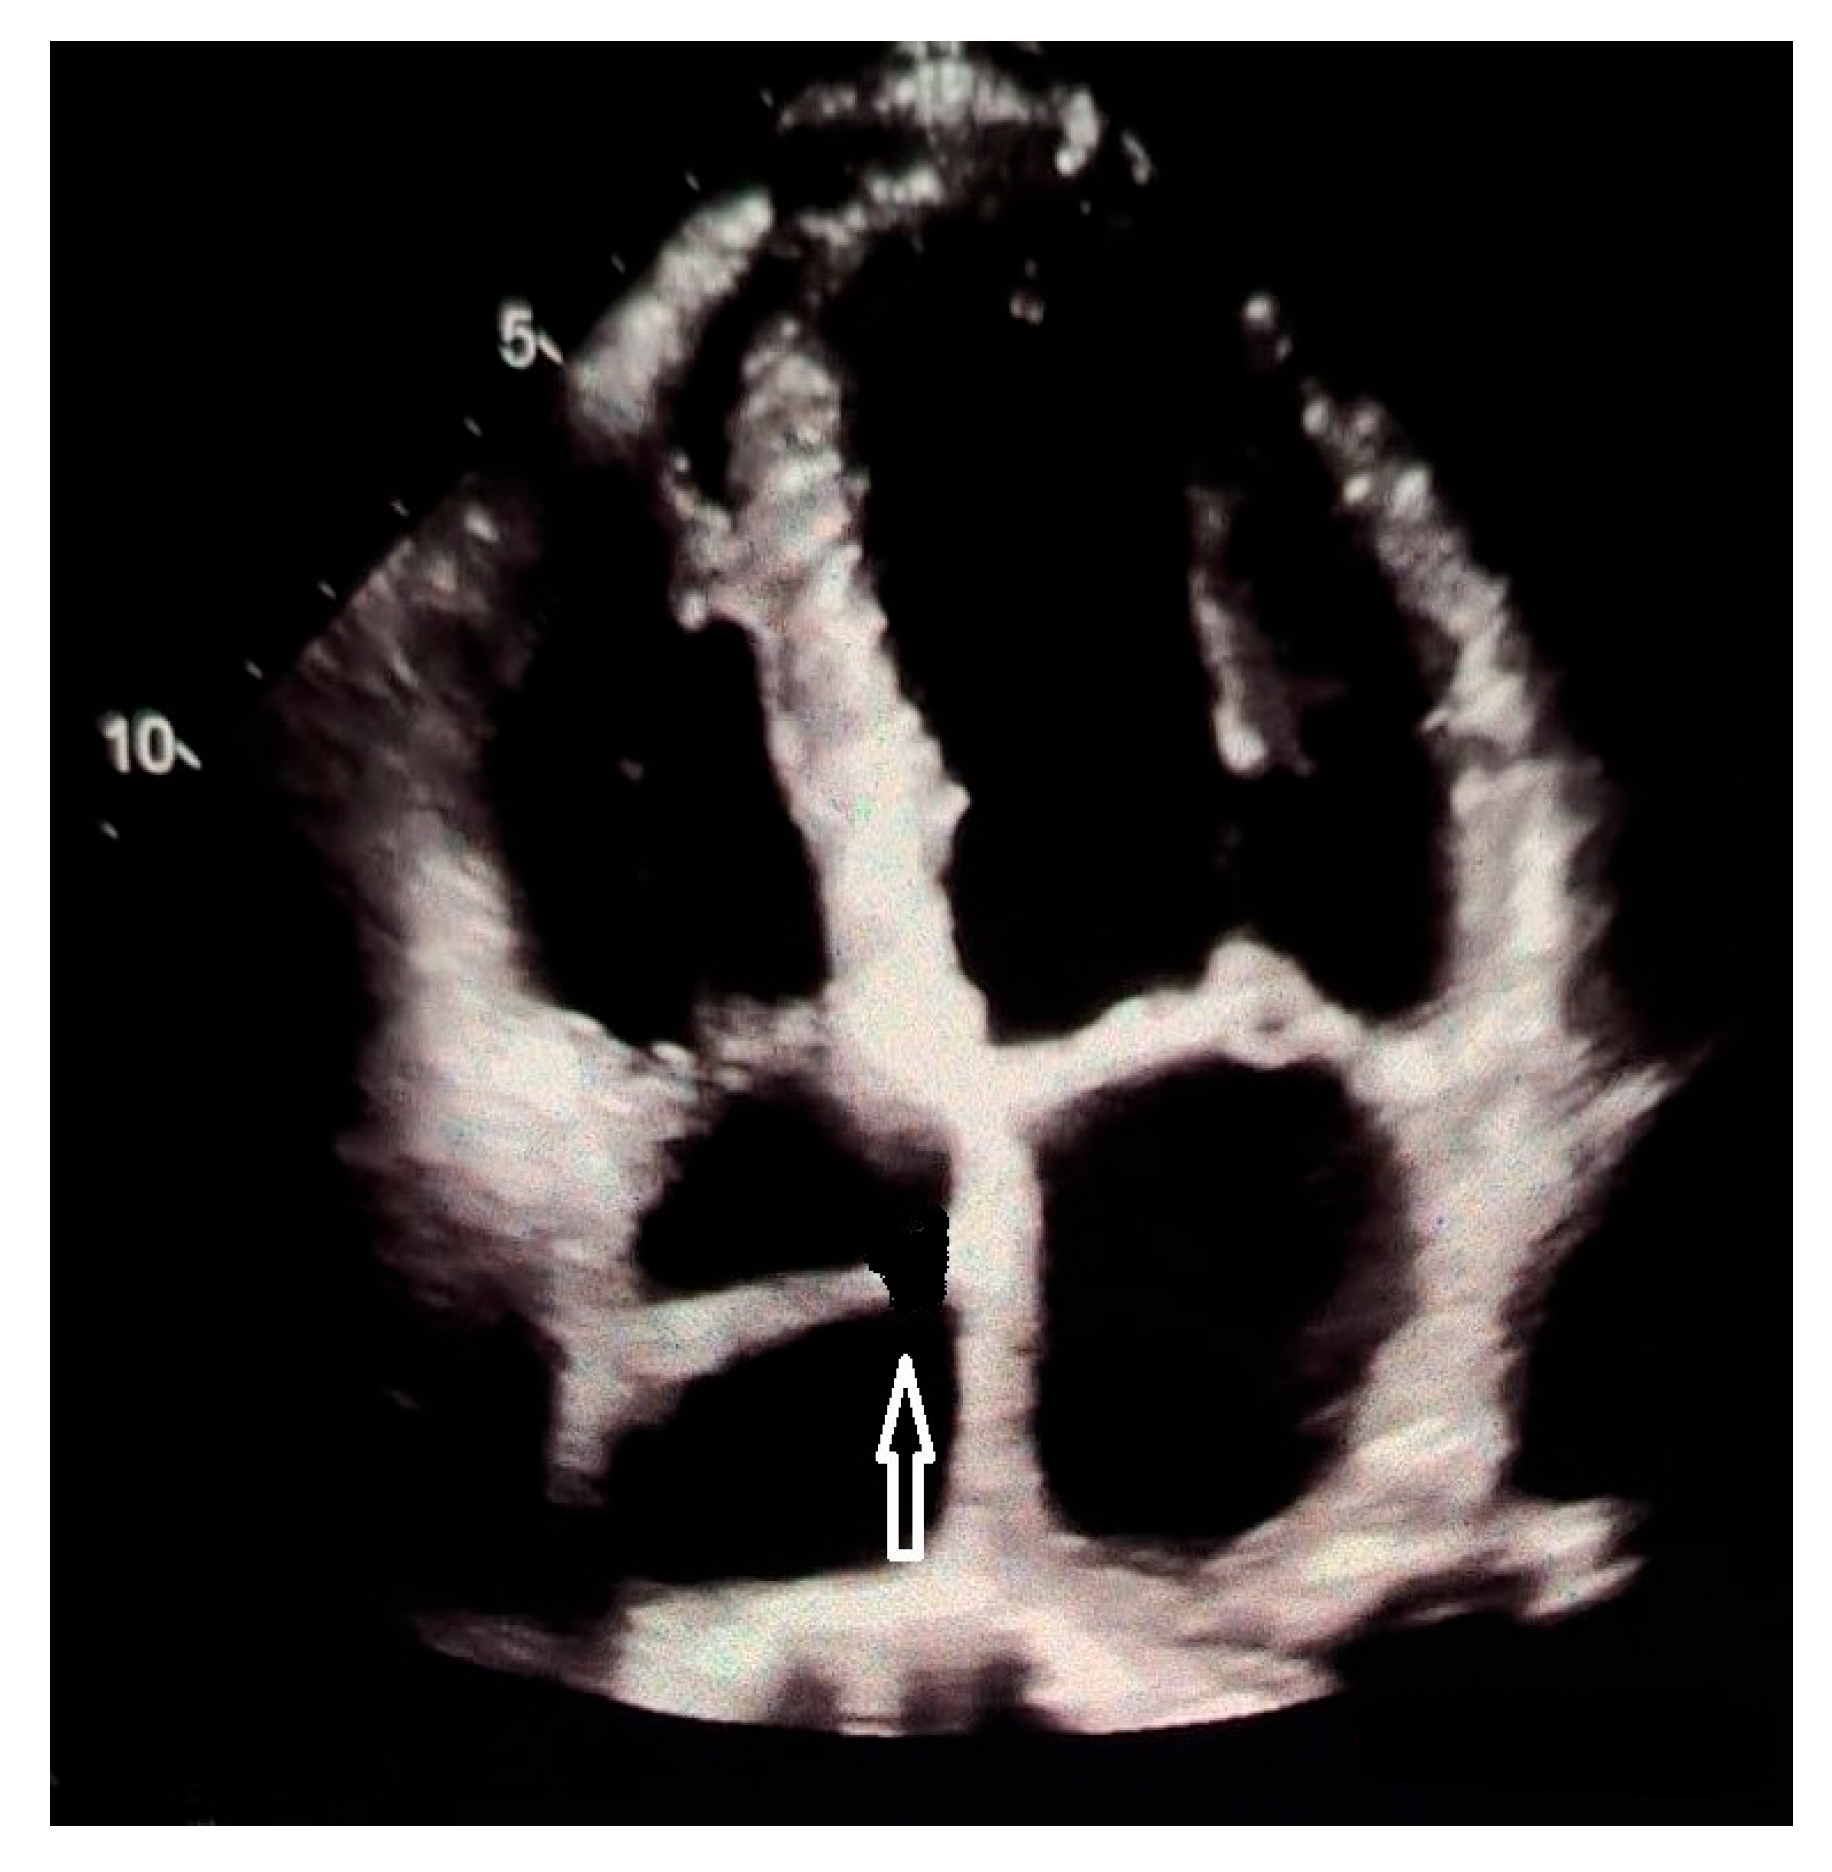

- Franco, E.; Rovera, C.; Moretti, C.; Bassareo, P.P. Arrhythmogenic Right Ventricular Cardiomyopathy and Cor Triatriatum Dexter: An Unreported Association. Clin. Case Rep. 2025, 13, e71159. [Google Scholar] [CrossRef]